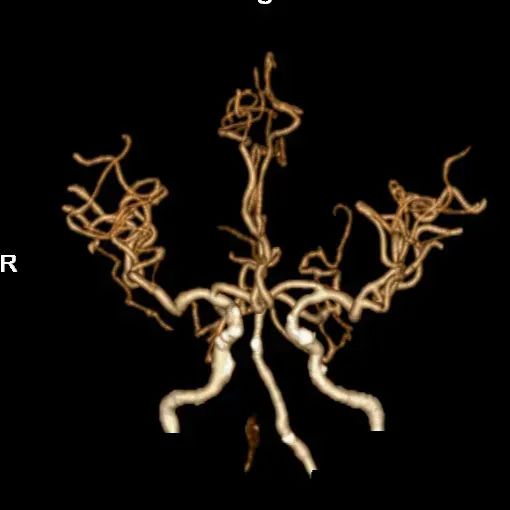

➢2024.07.09 入院急诊DSA:

造影见基底动脉中下段急性闭塞

造影见左侧优势椎动脉血流减慢

右侧椎动脉慢性闭塞

左侧颈内动脉无代偿

右侧后交通开放

术后4天,头颅CTA提示血管通畅。